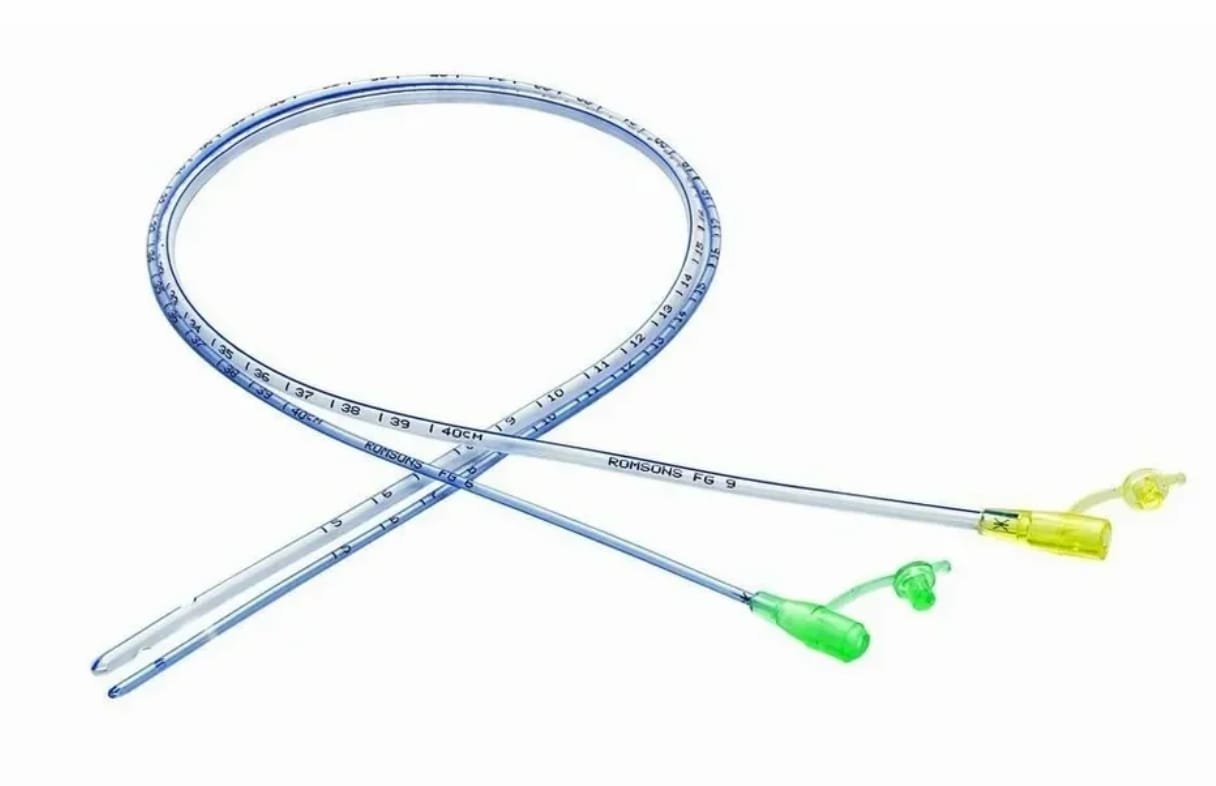

Nasogartric / Ryle's Tube

Nasogartric / Ryle's TubeOur ProductsFrom SurgicaveUplode:9 months ago from India